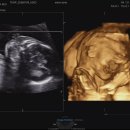

못했었구요, 황실 달력은 '아들'이라 하였는데 틀렸구요ㅎㅎ 입덧이 약하게 있기만 했지 입맛은 임신전과 크게 변하지 않았습니다. 또한, 피부는 중기인 지금...주셨답니다:) 저도 나중에 아기랑 트윈룩입고, 공주 옷 입히고, 같이 목욕탕도 갈 생각하며 겁나면서도 설레는 하루하루를 보내는 중이에요! 손으로 얼굴...

뮬로그(2026-02-25 14:00:00)